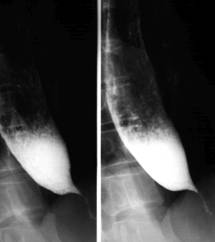

Fig.173 Stenoza esofagiana postcaustica

Zona de stenoza cuprinde un segment lung, localizat de obicei sub stramtoarea aortica. De cele mai multe ori este asociata cu stenoza gastrica antrala. Alteori se pot forma stenoze multiple, etajate.

Esofagul supraiacent este dilatat, in pilnie.